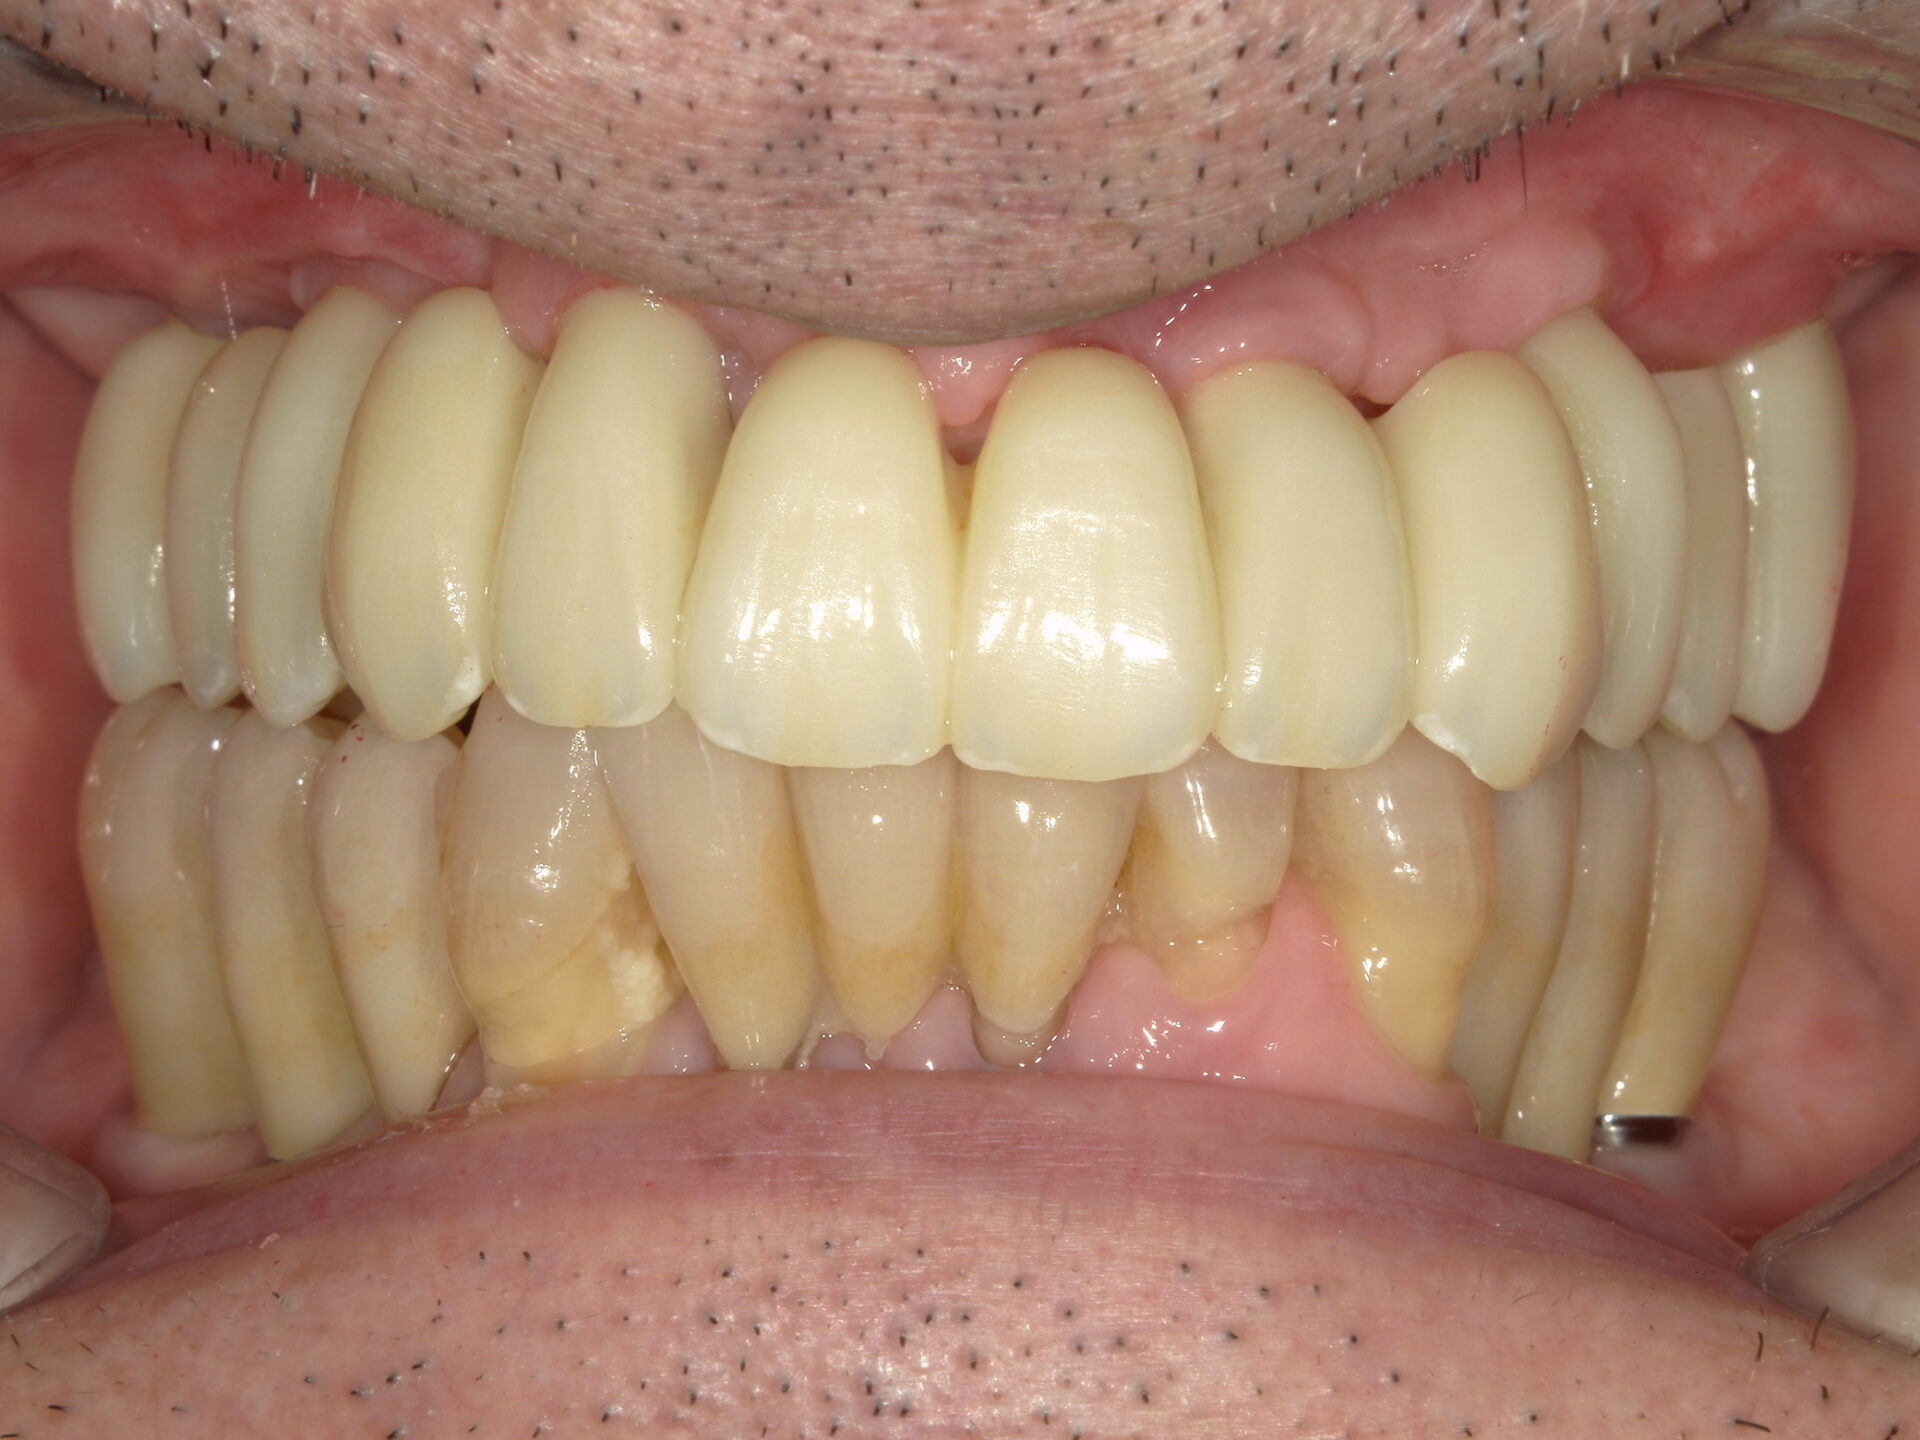

before

after

患者さんの年齢 50代 男性 症状 何も噛めない 治療内容 インプラント治療(オールオン4) 費用 費用900万(税抜) 治療期間・回数 治療期間2年・通院回数12回 メリット なんでも噛めるようになる 見た目が綺麗 デメリット・リスク 骨造成などで費用が増える場合がある - インプラント治療